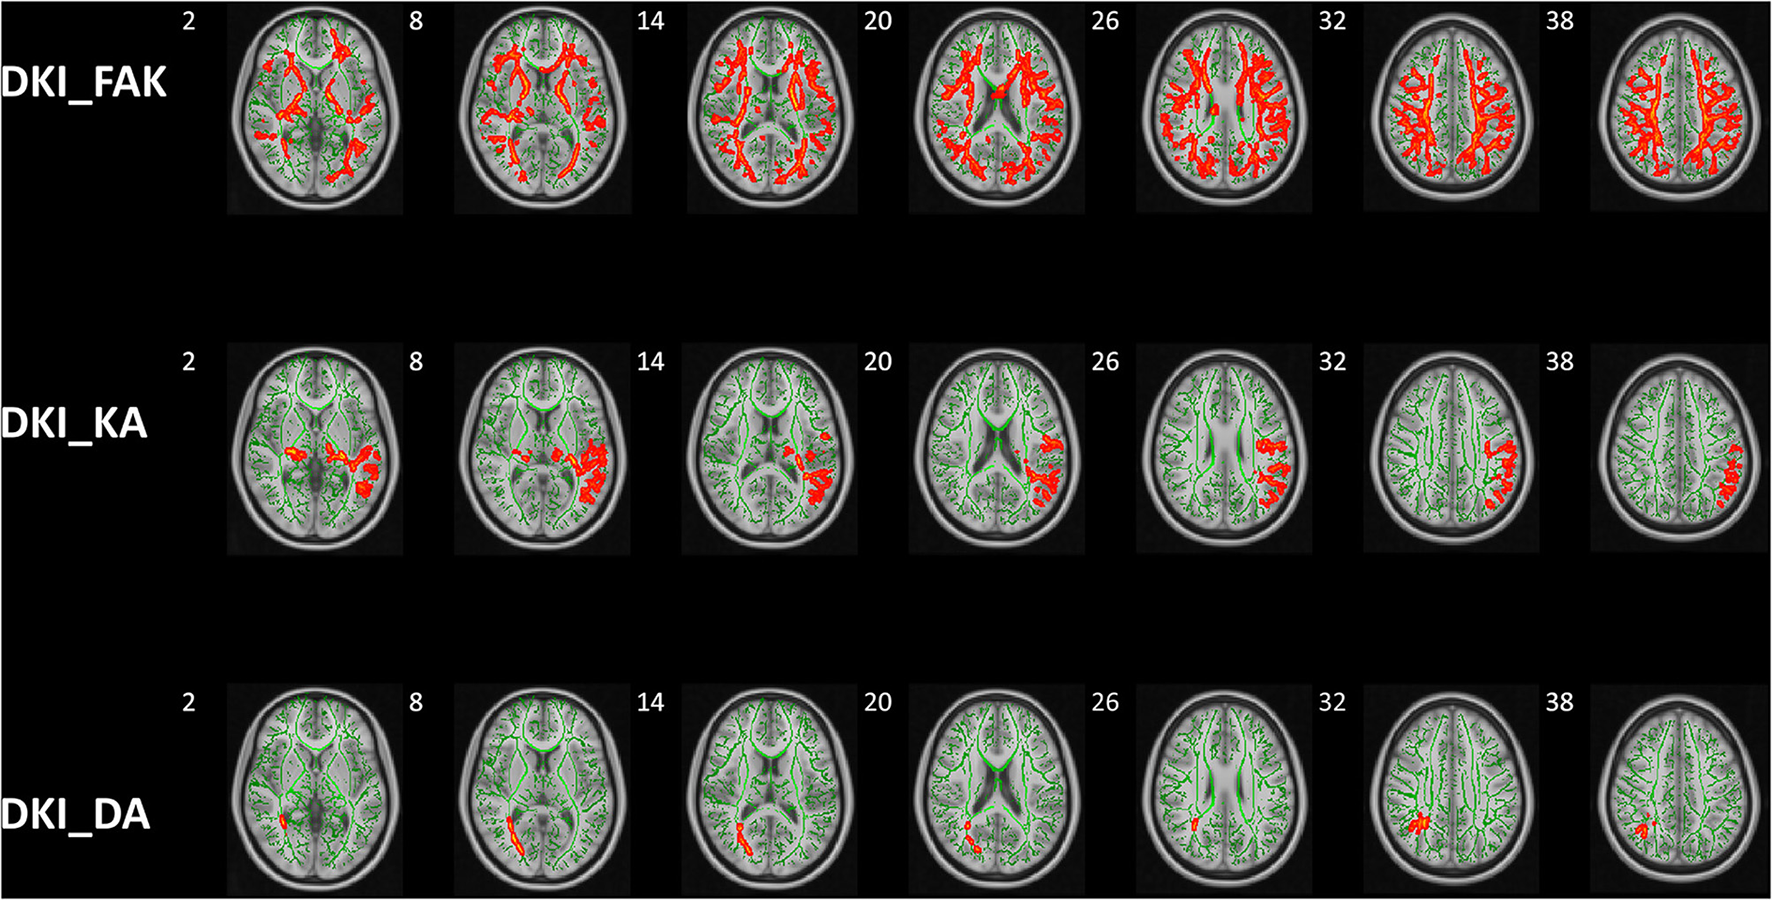

The significant clusters of subjects in Kurtosis fractional anisotropy are summarized in Table 2. Reduced Kurtosis fractional anisotropy (FAK) was observed in the bilateral CST, ATR, CG, HIP, IFOF, ILF, SLF, and UF, the temporal part of SLF as well as the FMA and FMI in ASD group in contrast to the healthy control group. We also found the ASD group showed significant axial kurtosis (KA) decrease in the bilateral CST, ATR, IFOF and the left SLF, ILF, UF as well as the left temporal part of SLF relative to the healthy control group (Supplementary Table 1). Compared to the healthy controls, the ASD group showed significant axial diffusivity (DA) decrease in FMA and the right ILF, IFOF, SLF, ATR as well as the right temporal part of SLF (Supplementary Table 2). In addition, the lateralization index (LI) of ASD group in the left SLF showed significant increase compared with healthy control group (Supplementary Table 3). No significant between group differences were observed in fractional anisotropy (Fa), radial diffusivity (RD), mean diffusivity (MD) and mean kurtosis (MK), radial kurtosis (KR). Figure 4 illustrated the group differences for the three parameters.

Figure 4

Group differences of TBSS in FAK, KA, and DA. Tract-based spatial statistics shows white matter regions with significant (p < 0.05, threshold-free cluster enhancement corrected) differences in FAK, KA, and DA values between ASD children and HCs. Green represents mean FA skeleton of all participants; red denotes parameters reduction in ASD children. DKI, diffusion kurtosis imaging; HCs, healthy controls; KFA, kurtosis FA; DA, axial diffusivity; KA, axial kurtosis.